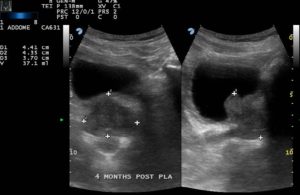

Caso Clinico n.1

Paziente affetto da IPB, con volume basale di 64 ml è stato trattato con Termoablazione con EchoLaser con due fibre per lobo.

Immagine ecografica pre trattamento

Immagine ecografica post trattamento a 4 mesi di follow-up

Il controllo di follow-up a 4 mesi dal trattamento ha evidenziato:

- una riduzione volumetrica da 64 ml a 37 ml

- residuo post-minzione da 200 ml a 43 ml

- IPSS score da 29 a 10

- Quality of Life (QoL) score da 5 a 1

- Massima velocità del flusso da 4 ml/s a 14 ml/s

- Assenza di complicazioni

Immagini per gentile concessione del Dott. Patelli (Ospedale Pesenti Fenaroli, Alzano Lombardo)